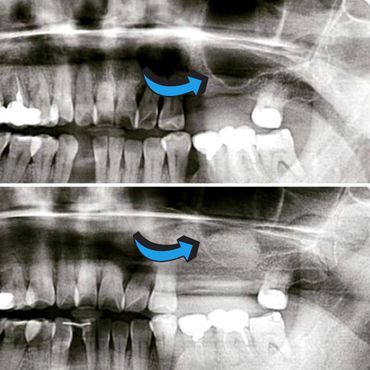

When natural teeth are lost, the face begins to show signs of aging due to bone loss. If you wait too long, the food chewing muscles begin to shorten to accommodate the reduced space between your nose and your chin. Missing one or more teeth could affect the overall health of the surrounding teeth and gums. A dental Implant is the solution to stop bone loss and restore the facial skeletal structure.

A dental implant is an artificial replacement of the root of a tooth. It is a viable option for people of all ages who are in good oral health. The implant is normally a cylinder-shaped metal post inserted and fused into the bone. A replacement tooth is then fitted onto it once it fuses into the bone. With the implant, one can eat, chew, and brush normally.

3. Preserve the remaining jaw bone and prevent resorption.